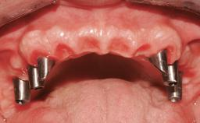

Fixed vs. Removable Prosthodontics for Restoring the Edentulous Maxilla

Fixed and removable prosthodontic implant therapy for restoration of the edentulous maxilla is both complex and challenging. Careful assessment and planning is needed in each individual case to explore whether a fixed or a removable solution will be the more suitable to satisfy the patient’s preference for optimal esthetics, phonetics, comfort and function. This Learning Pathway explores the prosthodontically driven treatment planning based on structured assessment, considered diagnosis and practical application in clinical case examples.